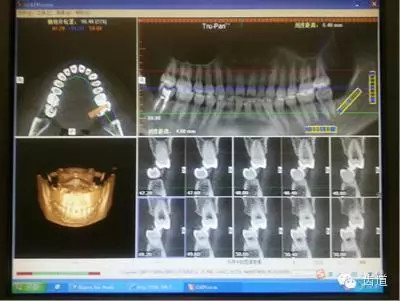

病例二:(權(quán)老師會診病例圖2、圖3)患者,女,24歲。主訴:左側(cè)顳下頜關(guān)節(jié)區(qū)張口疼痛,打哈欠時疼痛更明顯。從以下CBCT截圖中,我們能讀出哪些信息?

多位醫(yī)生均發(fā)現(xiàn):

左7正鎖合,47根管治療,中線不齊,切端對刃,下前牙扭,下前牙牙根吸收等問題。同時也提出一些疑問:前伸(牙合)是否有異常,髁突是否對稱,關(guān)節(jié)盤的位置是否正常等。

權(quán)老師指出:

通過CT和臨床檢查,患者覆蓋和覆(牙合)不足;開口度尚可,開口型呈“Z”型軌跡;左側(cè)咬肌區(qū)有輕微壓痛,無明顯彈響和其他雜音;髁突疑似吸收,升支似乎變短。初步診斷正鎖合是引起同側(cè)TMJ疼痛的原因。雖然信息有限,但我們依然可以從中學(xué)習(xí)到東西,用(牙合)學(xué)的思維去驗證和排除我們的疑問和猜想。